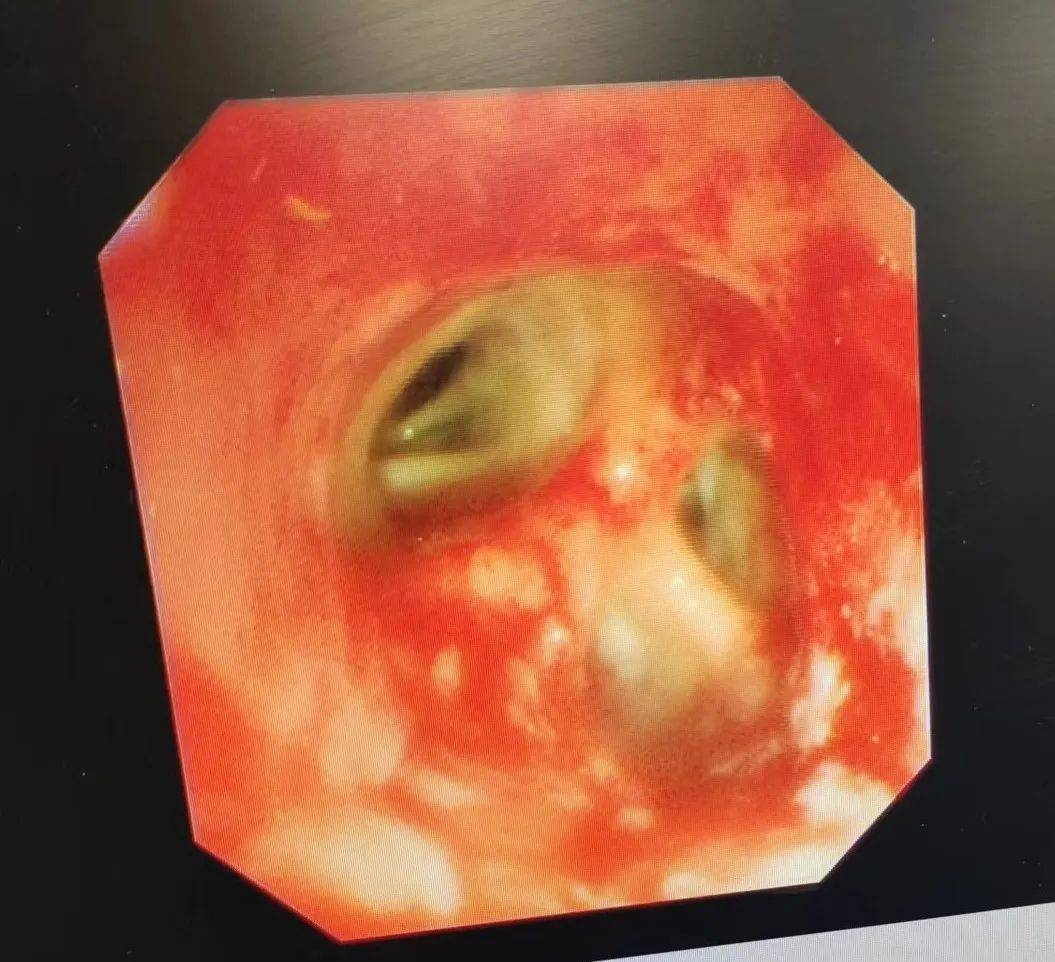

肺结石!淮安市一院成功开展首例硬镜下支气管结石取石术

图2 术中取出的支气管内结石图1 支气管镜见右肺中叶内侧段走行区高